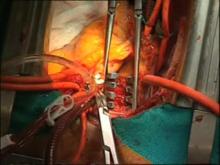

We present an alternative strategy, based on the application of a negative pressure in the left chambers and also in the superior vena cava to guarantee optimal azygos vein drainage. This makes it possible to avoid deep hypothermic circulatory arrest but achieves a bloodless surgical field. However, if needed, the core temperature may be lowered and circulatory arrest achieved.

The video shows how we surgically manage this pathology. It is very interesting to note that the PEA performed in the right pulmonary artery did not require circulatory arrest and in the left side it was achieved just for few minutes. That demonstrates the versatility of our technique. The extremely reduced back flow does not jeopardize the radical thrombus removal and the anatomic specimens confirm the efficacy of the technique. The avoidance or at least dramatic reduction of deep hypothermic circulatory arrest period is an obvious advantage.